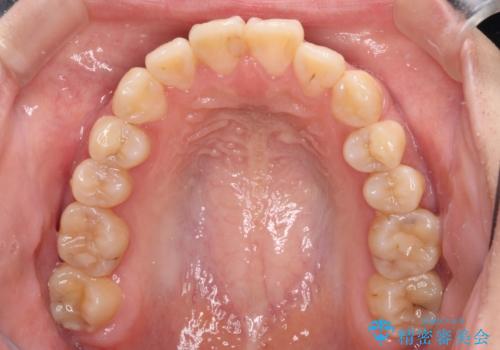

- 上下前歯の非接触と叢生を気にして来院された患者様です。

開咬の改善はインビザラインの最も得意とするところであるため、インビザラインを用いて矯正治療を行うこととしました。

治療開始直後に上顎前歯に激しい痛みが発現し、矯正治療を休んだり、マウスピースの装着時間を短くしたりと工夫をしましたが、残念ながら治療途中で失活していることが分かりました。

矯正治療の途中で前歯の根管治療とオールセラミッククラウンによる補綴治療を行い、その後インビザライン1セットを用いて細かい部分を仕上げました。